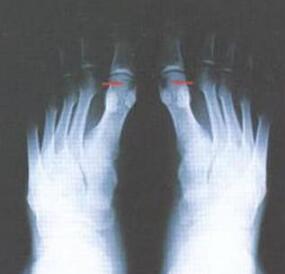

3年前,王先生出现右脚第一跖趾肿痛的现象,去医院诊断为“右足扭伤”,医生给予药物治疗,坚持服用半个月,疗效不明显,之后又出现左脚肿痛,行走不利,于是自行口服待因片等药物,疼痛缓解。...[详细]